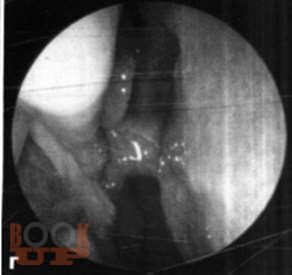

Методические рекомендации позволяют студентам, проходящим цикл практических занятий по оториноларингологии, помочь в освоении практических навыков.

Описаны подробные методики исследования носа, околоносовых пазух, глотки, гортани и уха, а также основные диагностические и лечебные манипуляции.